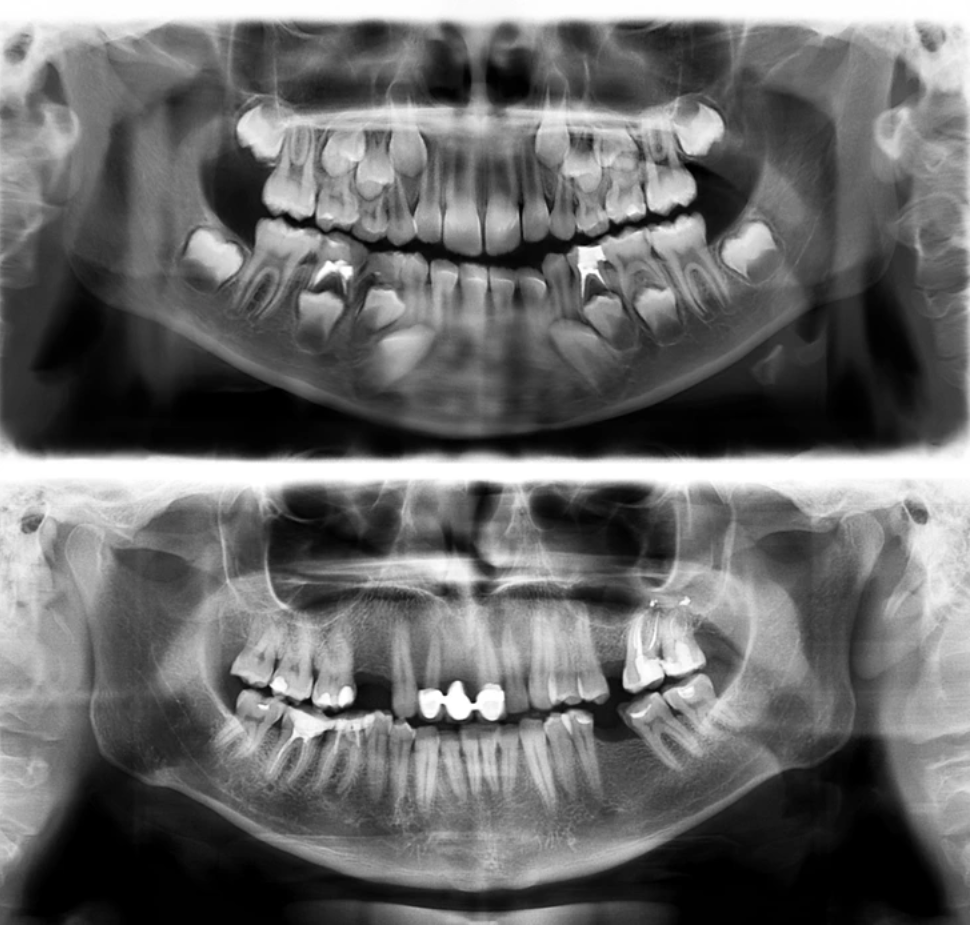

Так выглядят зубы человека в 7 (вверху) и в 30 лет